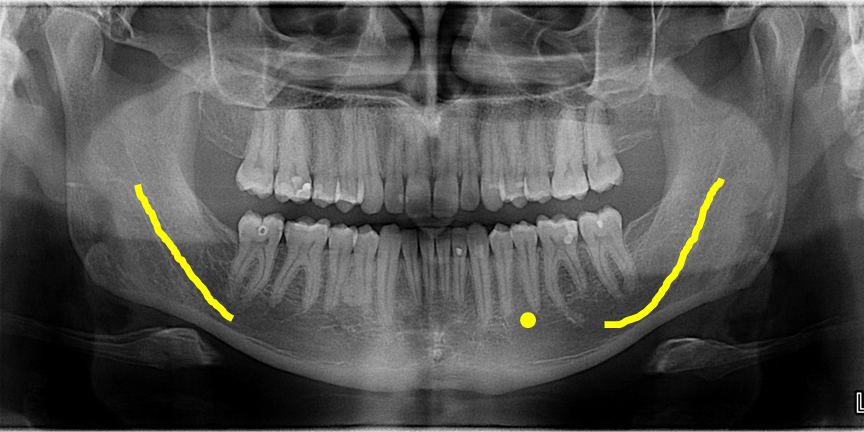

what are the bony landmarks of the mandible and surrounding structures

mandibular condyle

coronoid notch

coronoid process

mandibular foramen

lingula

mental foramen

mental ridge

mental fossa

lingual foramen

genial tubercles

inferior border of the mandible

mylohyoid ridge

external oblique ridge

angle of the mandible